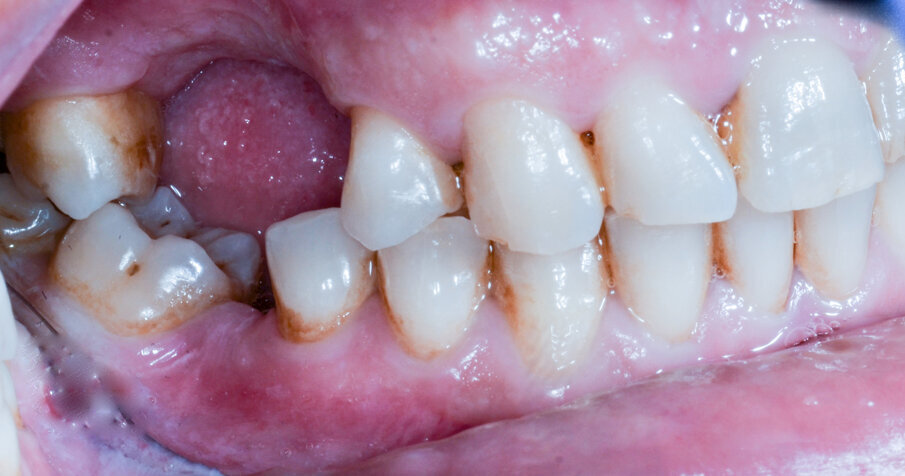

Il paziente R.V. di anni 40 affetto da Neurofibromatosi di tipo I, non fumatore e con neurofibroma palatino è reduce da intervento di avulsione dell’elemento 2.6 e cistectomia con concomitante socket preservation a cielo coperto ed inserimento sempre contestuale di impianto 2.5 in tecnica navigata; necessita per il completamento della riabilitazione dell’emiarcata superiore sinistra dell’inserimento di un secondo impianto in zona 2.6 (Figg. 1a, 1b). La ceratura diagnostica digitale evidenzia, già nel primo intervento, un importante compromesso estetico- igienico accettato dal paziente in virtù della firbomatosi da cui è affetto che ha scoraggiato qualsiasi procedura invasiva (un’esperienza personale nel trattamento del padre riporta un sanguimento difficilmente controllabile della mucosa affetta in corso di chirurgia a cielo aperto ed una guarigione dei tessuti particolarmente imprevedibile anche quando cheratinizzati; nulla è stato trovato al riguardo in letteratura). (Fig. 2).

Figg. 1a, 1b - Situazione iniziale.

Fig. 16 – L’impianto subito dopo il suo posizionamento in chirurgia flapless; approccio preferito in questo caso per l’imprevedibilità della guarigione come già espresso nel testo.